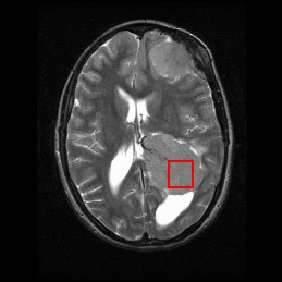

Shown below is an MRI brain scan (in the axial plane, that is slicing from front-to-back and side-to-side through the head) showing a brain tumor (meningioma) at the bottom right. The red box shows the volume of interest from which chemical information was obtained by MRS (a cube with 2 cm sides which produces a square when intersecting the 5 mm thick slice of the MRI scan).